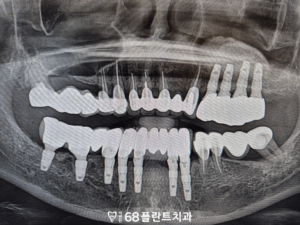

그리고 이식한 뼈와 임플란트가

자연스러운 치유 과정을 거쳐

내 뼈에 단단히 고정된 것이 확인되면,

그 위에 맞춤형 보철물을 올려

치아 본연의 씹는 기능과 심미성을

회복할 수 있도록 보철 작업을 시작하게 됩니다.

◆ 전 > 후 ◆